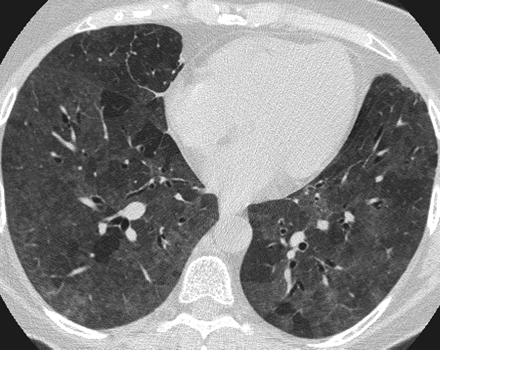

У переболевших COVID-19 без симптомов обнаружены поражения легких, сообщили японские ученые, изучавшие результаты компьютерной томографии заразившихся коронавирусом пассажиров лайнера Diamond Princess.

Из 104 человек, подхвативших инфекцию на корабле, у 76 болезнь протекала без симптомов. Однако у большинства «бессимптомных» пациентов (41 человек) в легких нашли изменения — «эффект матового стекла».

Исходя из этих данных, японские ученые пришли к выводу, что и при бессимптомном течении болезни легким наносится вред, сообщает ТАСС.

Симптом «матового стекла» — неспецифический радиологический симптом, отражающий различные патологические изменения в легочной ткани на уровне альвеол. Визуализируется при компьютерной томографии как туманное, матовое снижение прозрачности легочной ткани с дифференцируемым рисунком сосудов и бронхов на этом фоне.

Пневмонии и пневмониты любой этиологии (бактериальной, вирусной, грибковой и т. д.) являются одной из наиболее распространенных причин фокального или диффузного симптома «матового стекла», который может отражать либо неполное заполнение просвета альвеол содержимым (при начальных или остаточных воспалительных проявлениях), либо инфильтрацию альвеолярных стенок (внутридолькового интерстиция).